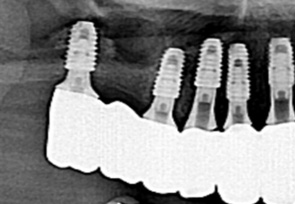

임플란트에서 뼈 이식은 거의 대부분의 경우 필요합니다. 치아가 상실된 후 시간이 경과하면 치아를 지지하고 있는 치조골의 양과 질의 상태가 함께 나빠집니다. 이처럼 약해진 잇몸뼈에 임플란트 수술을 하게 되면 단단하게 고정이 되지 않기 때문에 임플란트 수술의 효과를 볼 수 없게 됩니다.

이때, 약해진 잇몸에 인공뼈 이식을 통하여 임플란트 식립이 가능하게 됩니다. 뼈의 밀도가 치밀하고 단단할 수록 임플라트의 성공률은 높아지기 때문에 뼈이식을 통하여 임플란트 시술 환경을 조성하게 됩니다.

임플란트 시술은 임플란트 시술부위 잇몸뼈가 최소 1mm 이상일 때 시술이 가능합니다. 하지만 임플란트 시술이 이루어지기에 충분하지 못할만큼 흡수가 일어나 잇몸뼈가 얇아지고 약해진 경우 ‘뼈 이식(골이식)’을 통해 임플란트에 적합한 뼈의 두께를 확보할 수 있습니다.

미국치과 임플란트 학회(AAID)의 인정의(AF. Associate.Fellow)인 일등플란트치과의 한순일 대표원장이 다 년간의 많은 임상경험 노하우를 바탕으로 구강 상태에 따른 적합한 뼈이식을 통해 임플란트에 적합한 뼈의 두께를 확보한 후 식립을 합니다.